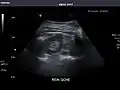

Kidneys: Right and left kidneys measure 11.5 cm and 12 cm in length respectively. No hydronephrosis. Small left lower pole kidney cyst.

Right kidney

Left kidney